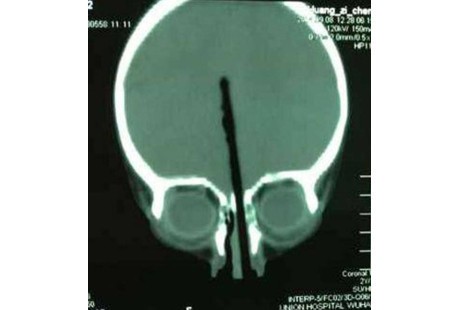

Untuk mengambil sumpit yang tertancap di hidungnya, Zicheng harus menjalani operasi yang berlangsung beberapa jam. Hebatnya, saat operasi tidak ditemukan kerusakan di saraf utama serta arteri bocah itu.

Kemungkinan Zicheng pulih total pun terbuka lebar dan hal ini membuat sang ayah senang. Meski demikian, sampai saat ini ayah Zicheng masih belum mengetahui bagaimana bisa tiba-tiba sebatang sumpit bisa melesak ke hidung anaknya.